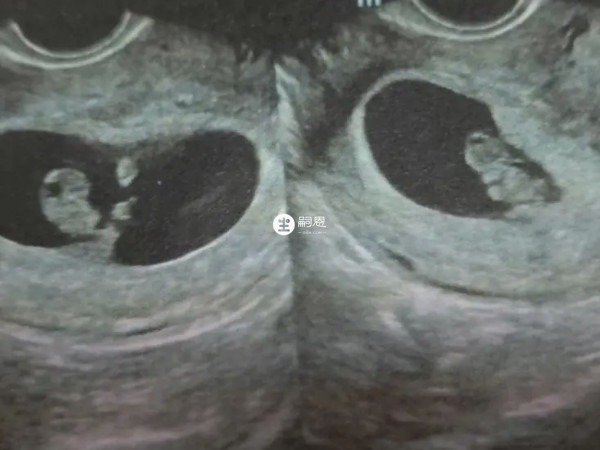

孕囊也叫胎囊,是胚胎最初的形態,那時候胎兒還沒有形成,不過隨著胎寶寶的生長髮育,孕囊也會跟著變化,據網傳說孕囊大小可以判斷男女,為此部分人為了讓說法更具有一定的科學性,還總結了一套懷孕50天孕囊大小看男女的方法,具體參考方式如下,有需要的孕媽媽可以作為一種娛樂參考:

懷孕50多天的時候,處於孕早期階段,通過超聲看孕囊大小一般波動在24-31mm左右,此時需要核對孕周是否準確,然後判斷孕囊大小是否符合正常生長範圍。

如果這時的女性想要通過孕囊大小來辨別男女的話,往往是不準確的,這時因為有的孕婦看胎囊圓的,最後卻生男寶,而有的孕婦判斷出來是長的,最後卻生了女寶,由此可見,50天看胎囊判斷男女準確性並不高。